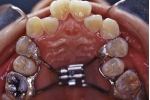

構造

歯に付けたリング状の薄い金属板(バンド)と金属ワイヤーで出来ています。患者様の歯形をお取りして、石膏模型の上で予め製作したものを取り付けます。

歯並び全体の横幅を維持するために用いる装置です。奥歯が手前に倒れてこないように、固定源を強化するために用いるときもあります(加強固定と言います)。最も幅の維持が必要な位置に取り付けますので、装置の固定されている位置や形態はいろいろですが、装置の基本構造は同じで、写真のように上顎の裏側の形に合わせて少し太めの針金(0.8-1.2mmくらい)を沿わせ、奥歯に固定したバンドと一緒に一体化させて留めてあります。患者さんが自分で取り外すことはできませんが、調節が必要なときは先生が外して、調整後また留め直すという操作を繰り返していきます。